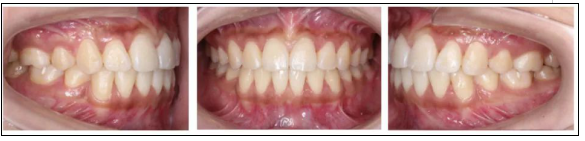

2.* 口內(nèi)檢查(以及調(diào)節(jié)前后口內(nèi)對比):

* 口內(nèi)檢查(以及調(diào)節(jié)前后口內(nèi)對比):

矯正前

口腔衛(wèi)生稍差,軟垢色素(+),牙齦略充血、腫大;恒牙列;左側(cè)磨牙遠(yuǎn)中關(guān)系,右側(cè)磨牙中性關(guān)系;前牙開牙合、深覆牙合;上下牙弓尖圓型;上下牙列輕度擁擠;上中線基本正,下中線左偏。

矯正后

上下牙列齊,前牙覆牙合覆蓋正常,中線正,雙側(cè)尖牙及磨牙關(guān)系中性,雙側(cè)后牙尖窩關(guān)系良好。